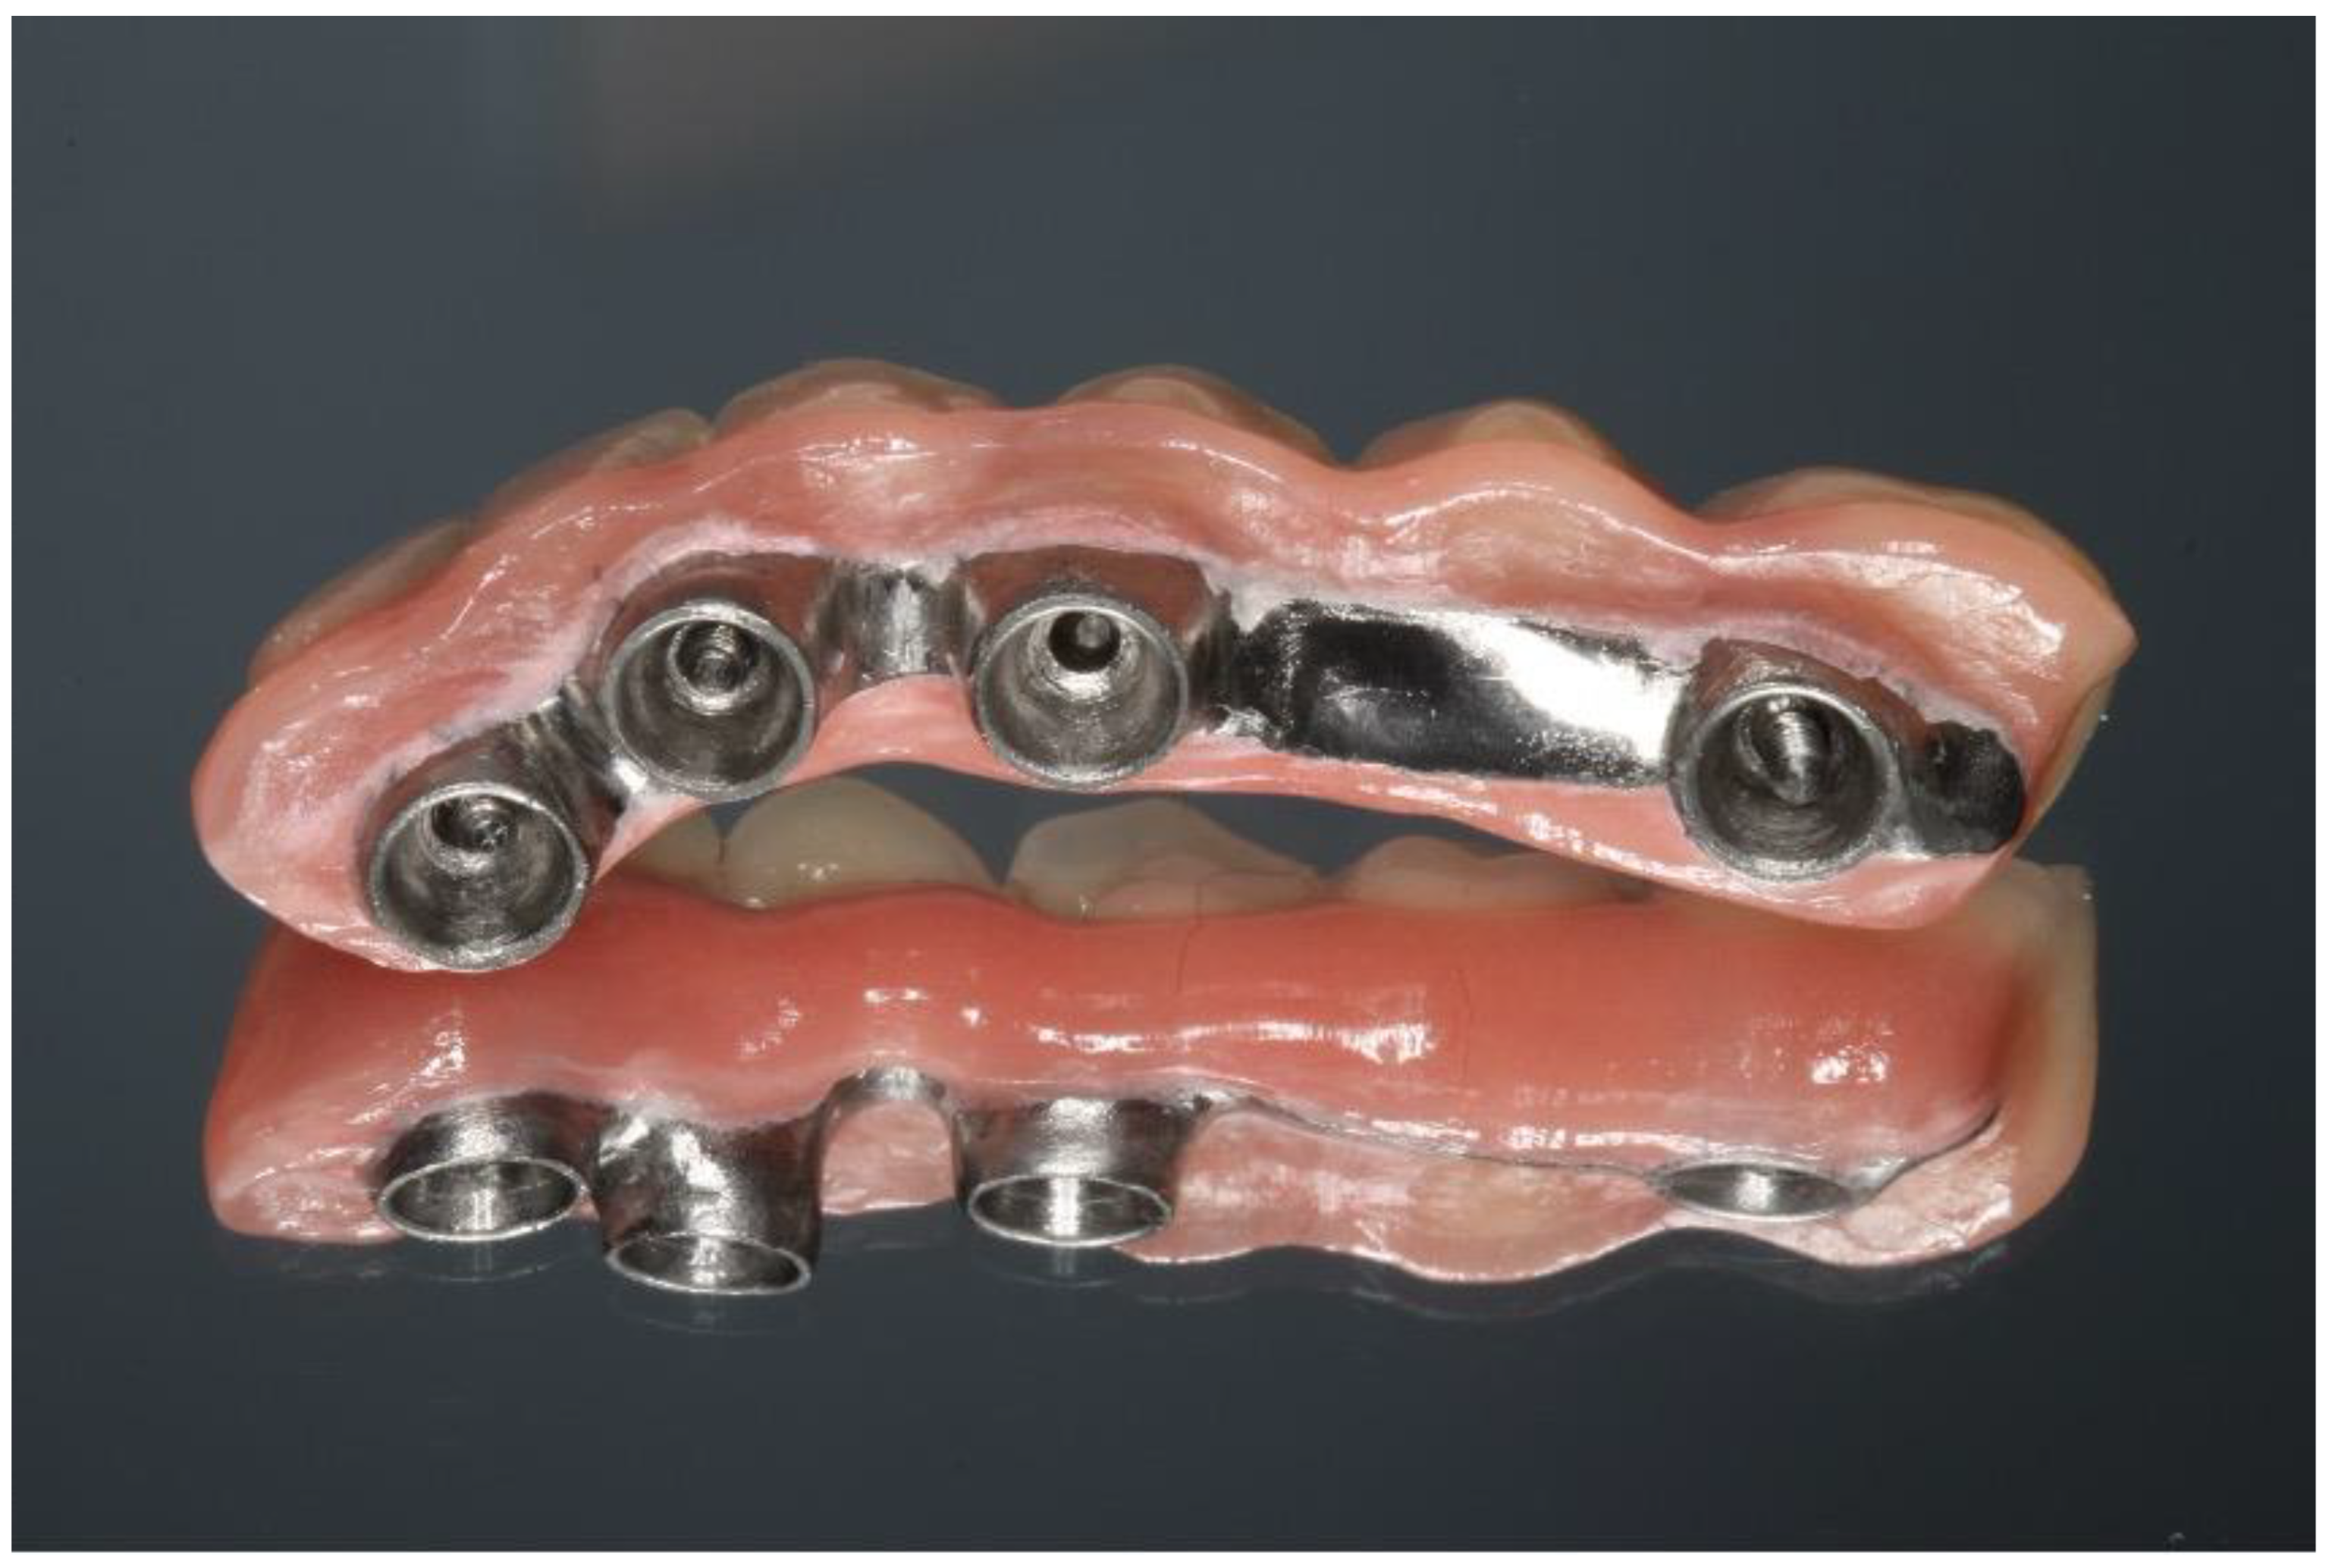

2.2. Case 2